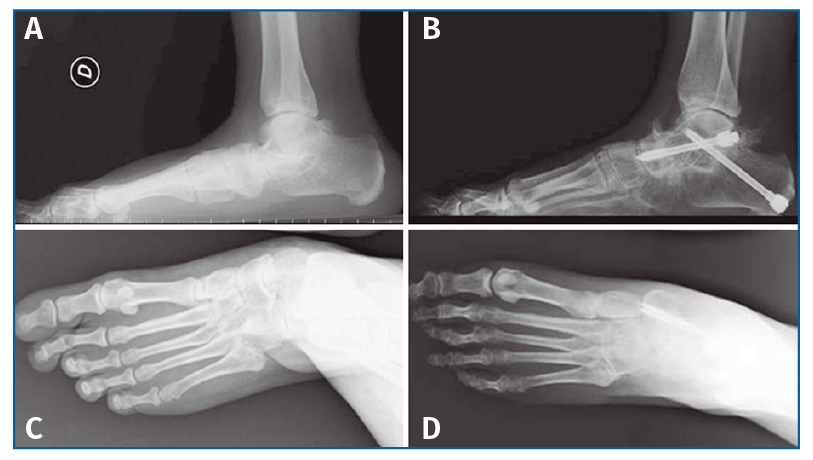

No se pudo realizar una valoración completa del resultado de la corrección clínica por no disponer de fotografías pre- y postoperatorias de todos los pacientes (Figura 5), aunque, como hemos comentado anteriormente, se valoró la evolución radiológica en la totalidad de los pacientes (Figura 6).

Figura 6. Aspecto radiográfico pre- (A y C) y postoperatorio (B y D) mostrando la corrección de las mediciones angulares.